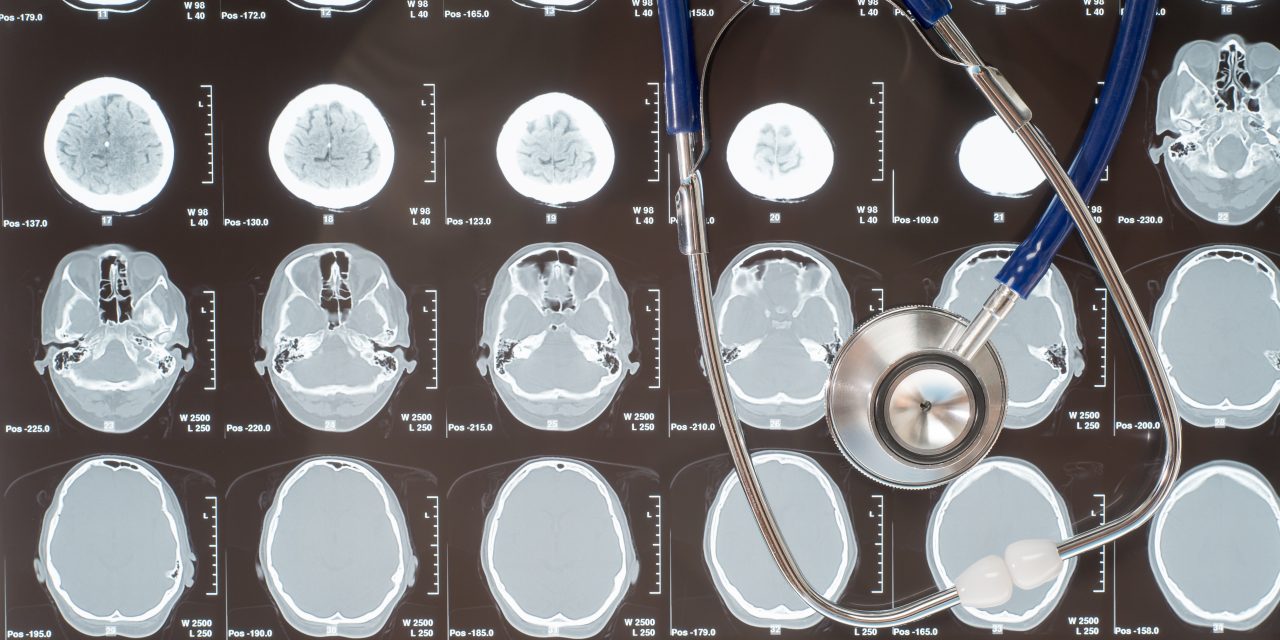

A modern diagnosztikai lehetőségeknek köszönhetően ma már gyorsan és pontosan meghatározható, hogy milyen jellegű problémáról van szó, így a kezelés is célzottabbá válhat.